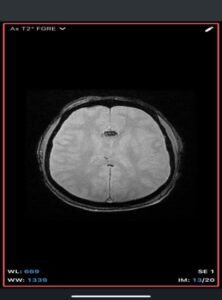

Intracranial dermoid cyst

A rare, congenital, benign lesion composed of mature adipose tissue located within the pericallosal cistern, closely related to the corpus callosum. It is a developmental anomaly rather than a true neoplasm.

Imaging Findings-

- MRI

- T1-weighted: Hyperintense (fat signal).

- T2-weighted: Variable, usually hyperintense; may show chemical shift artifacts.

- Fat-suppressed sequences: Complete signal suppression confirms fat composition.

- Post-contrast: No enhancement.